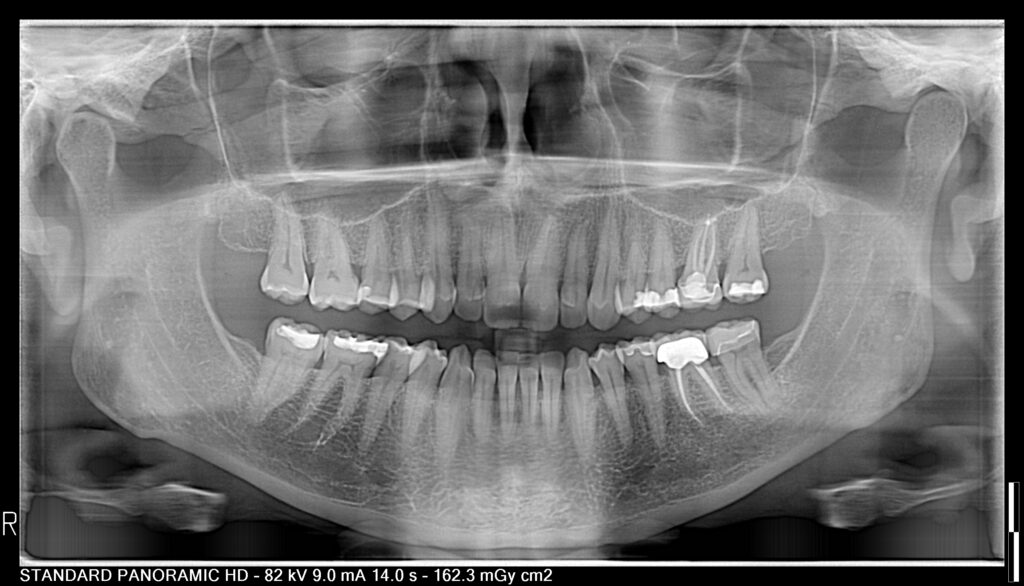

In my practice, I saw many patients for a second opinion who were confused by other dental treatments proposed to them.

“Why do I need a crown if my tooth doesn’t hurt?”

You’re not alone! Let me (Dr. Hannan) provide FREE and honest advice about your dental concerns. What do you have to lose?